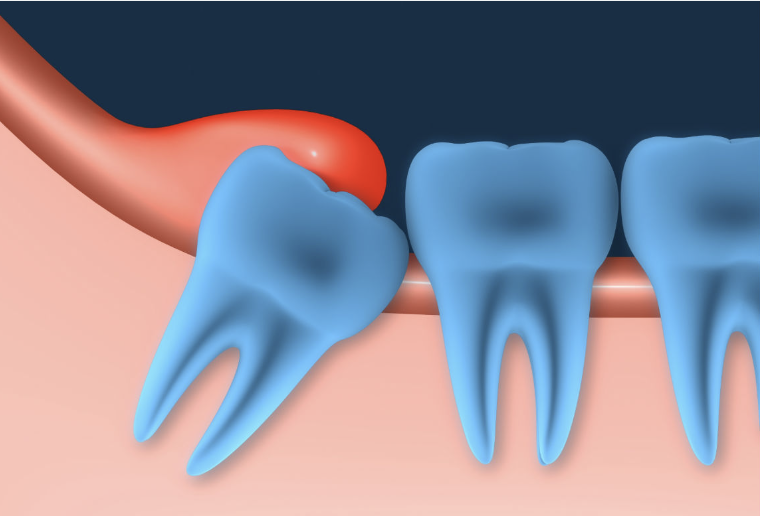

Wisdom teeth are notoriously painful. They seem to come whenever they please, and when they do, they can easily wreak havoc. Pericoronitis is an infection that can occur when your wisdom teeth don’t come in properly. The risk of this spreading is too high to neglect.

If you get it, you’ll know because of your irritated gums in that area, as well as possible bad breath. You'll likely feel a painful pressure in your wisdom teeth area also. See a dentist as soon as possible to get this resolved.

Growing wisdom teeth can be painful and may result in pericoronitis, an infection that can spread if left untreated. If your gums in the wisdom tooth area are inflamed, and you have bad breath, it could be a sign of pericoronitis caused by the infection. You may also experience painful pressure in the wisdom teeth area. Contact our office and make an appointment to see us as soon as possible to address the issue and obtain relief from the discomfort.